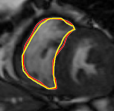

IV-A Tracking Multiple Regions

In cardiac image analysis, there are multiple structures (the right and left ventricles, and myocardium) that all useful and should be segmented. Our method is easily adaptable to this case. Indeed, computation of in Section III-C can be readily generalized. In general, multiple level sets should be used to represent multiple regions. However, in our case of interest (ventricles and surrounding epicardium), the regions form a rather simple topology (see Figure 3), and all regions can be represented using a single level set.